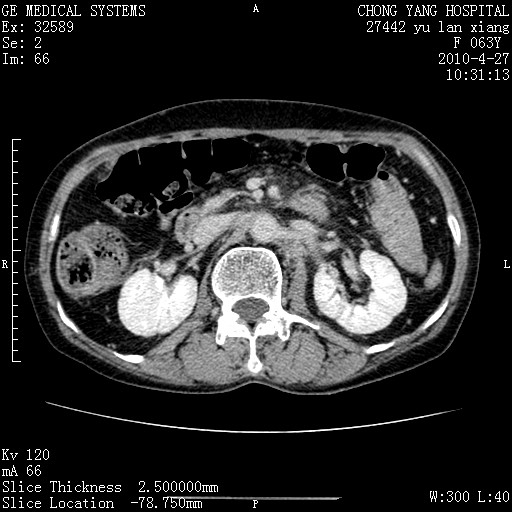

标题: CT26066:F63Y 上腹正中压痛半月,CA199:7400u/ml,MR示胰腺炎伴 [打印本页]

胰腺癌侵犯腹腔动脉干-分支、胃壁、左侧膈肌伴胰周及腹膜后淋巴结转移、胆囊切除术后。

胰腺癌侵犯腹腔动脉干-分支、胃壁、左侧膈肌伴胰周及腹膜后淋巴结转移、胆囊未显影。